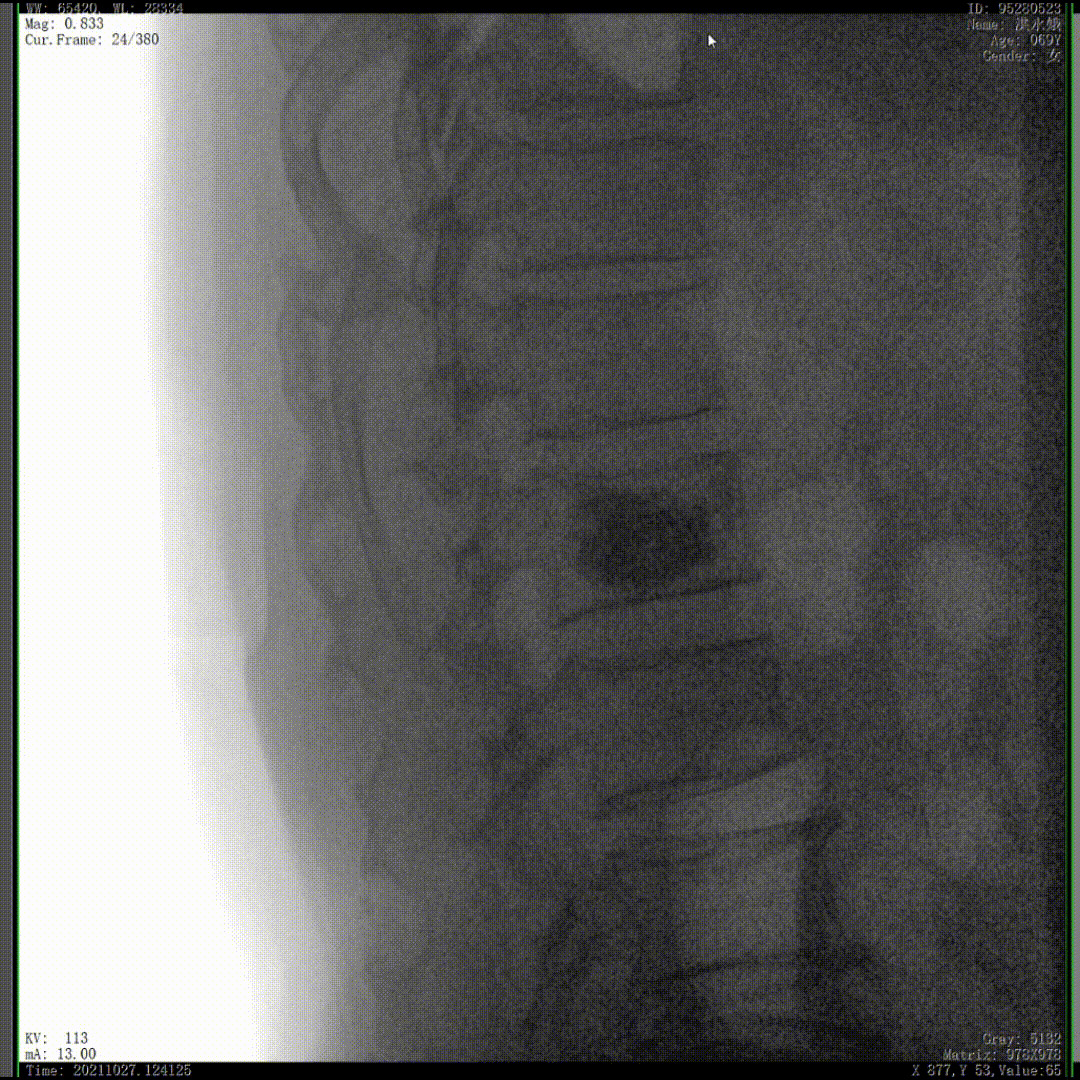

我們完成了椎體成形術以后,在二維的正側位影像上還不能看清骨水泥的滲漏情況,通過三維影像就可以360°的觀察骨水泥在椎體里到底是怎么彌散的。如果當時我們判斷出來質量不好,可能還需要進行翻修,這是在二維影像上不能看到的。